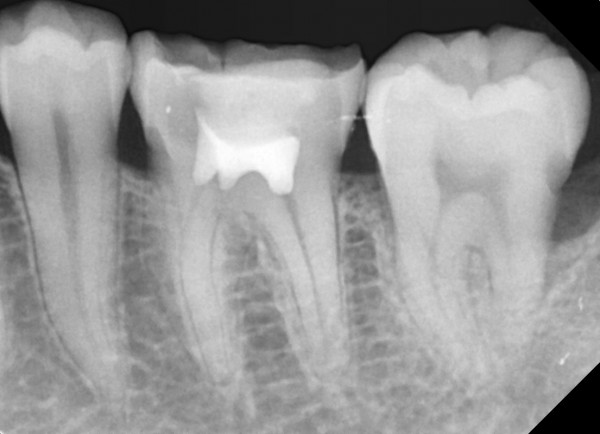

충치치료&신경치료 하루에 끝나는 신경치료

60bab75a1a70db4a6fd0ef2b4df1f9ae_1767345003_6216.jpg